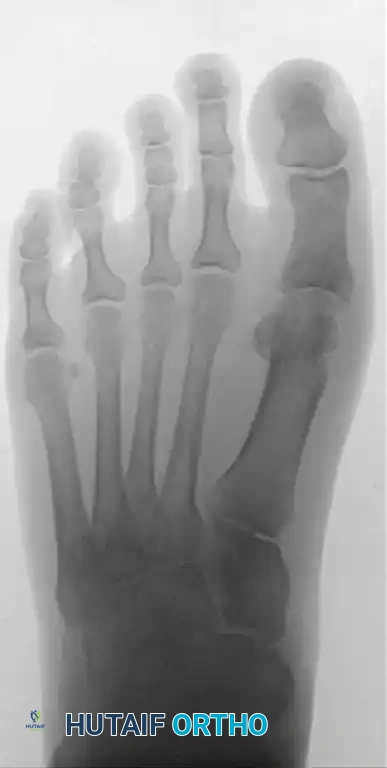

Post-op X-ray A

Post-op X-ray B

Post-op X-ray C

Figures 9-11: Immediate postoperative AP, Lateral, and Oblique radiographs demonstrating adequate dorsal metatarsal head resection and joint decompression.